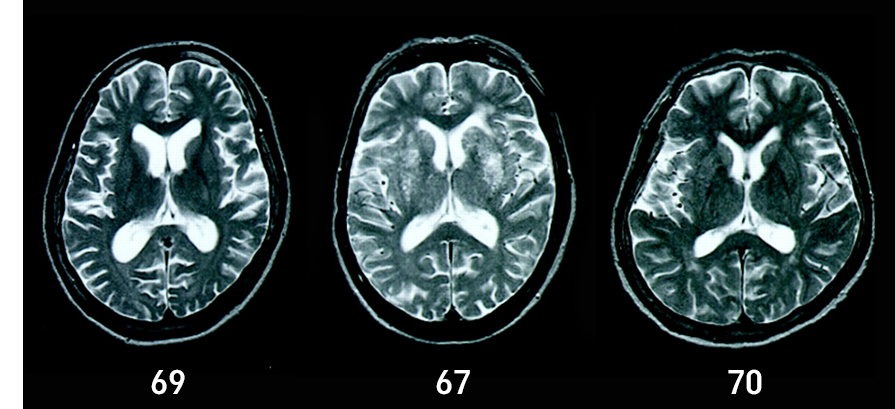

| Áø´Ü | ȯÀÚ¿¡ ´ëÇØ °¡Àå Àß ¾Ë°í ÀÖ´Â º¸È£ÀÚÀÇ º¸°í¸¦ ÅëÇÑ Á¤È®ÇÑ º´·Â ûÃë°¡ ¸Å¿ì Áß¿äÇÔ |

| °Ë»ç |

½Åü°Ë»ç¿Í ½Å°æÇÐÀû °Ë»ç Á¤½Å»óÅ °Ë»ç ÀÏ»ó»ýȰµ¿ÀÛ Æò°¡ Ç÷¾× °Ë»ç µîÀÇ ½ÇÇè½Ç °Ë»ç ³ú¿µ»óÇÐ°Ë»ç ½Å°æ½É¸®°Ë»ç |